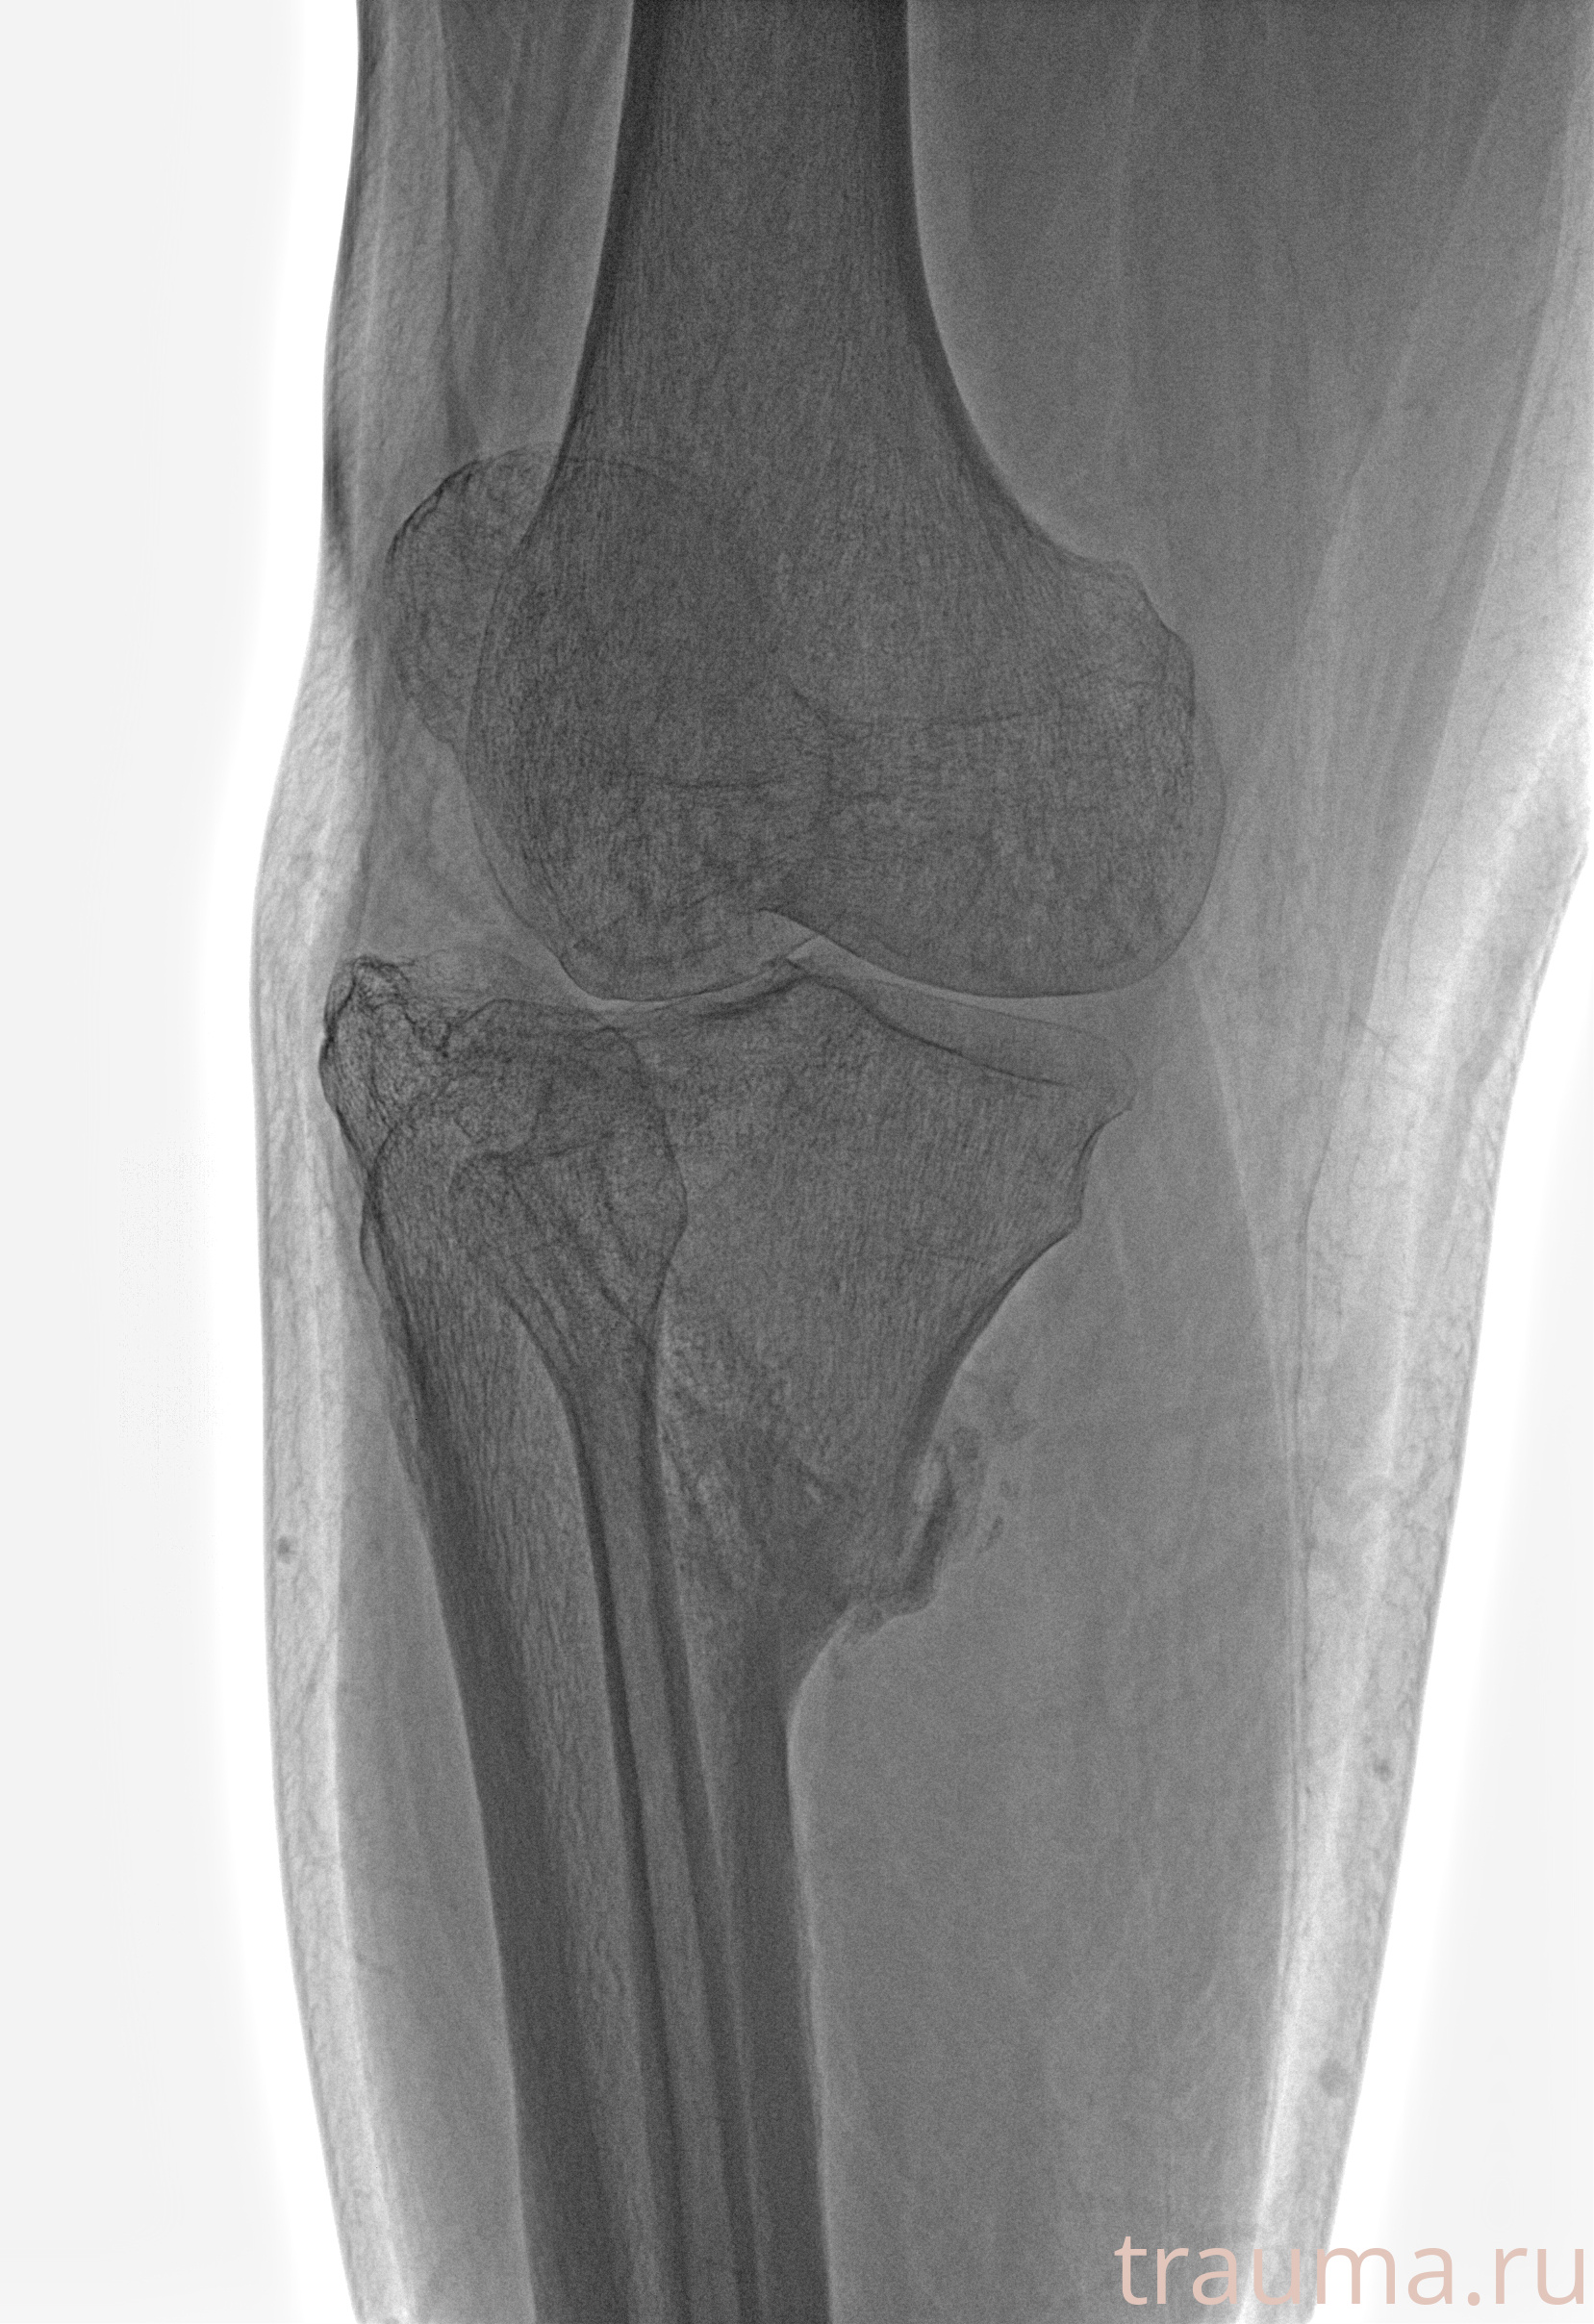

Рентгенограммы

Рентген на дому: по вашему адресу приезжает врач-рентгенолог, травматолог-ортопед с мобильным рентгеновским аппаратом, проводит диагностику травмы или заболевания, делает необходимые рентгенограммы, дает рекомендации по дальнейшему лечению. Получить качественные снимки в домашних условиях возможно благодаря уникальной методике, разработанной МосРентген Центром для института  Склифосовского